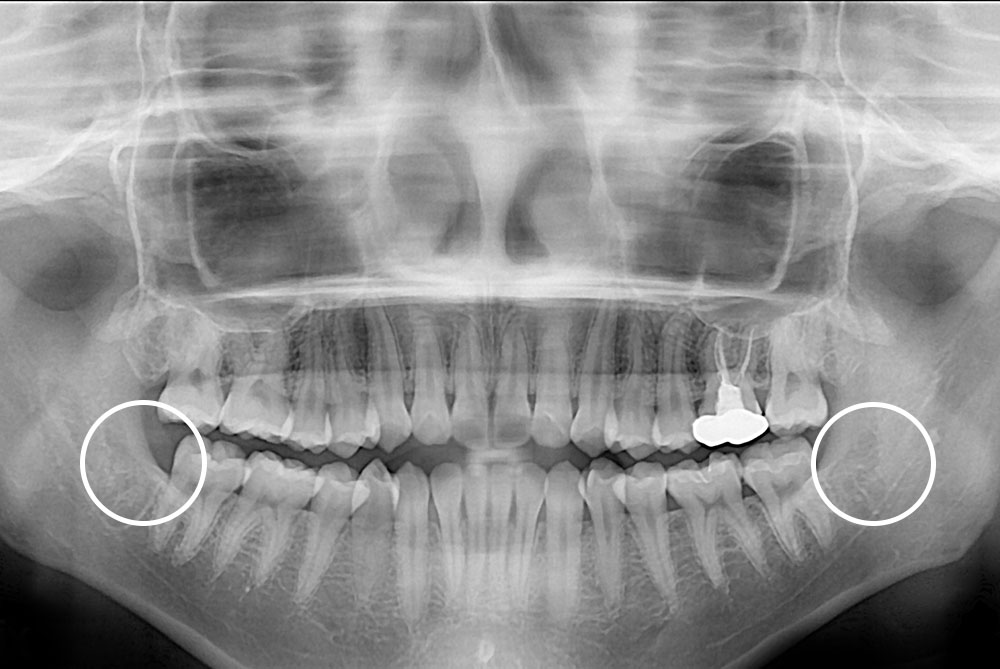

[사랑니] 매복 사랑니 발치

치료전 : 2019-02-27